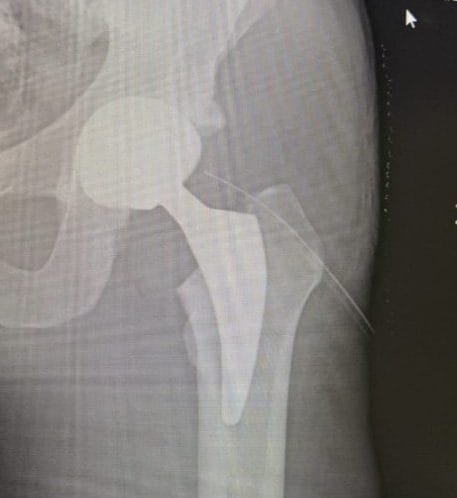

L'ex giocatore della Roma ha pubblicato sui social le immagini dall'ospedale, con tanto di radiografia dove si vede la una protesi metallica che dovrebbe aiutarlo da ora in avanti. "Spero che sia l'inizio di una vita senza dolore" scrive, un messaggio toccante per un calciatore che per tanto tempo ha dovuto condividere con il dolore cronico che gli ha impedito di giocare come voleva.

Ma da oggi Lamela è ottimista sul futuro perché si è sottoposto a un'operazione all'anca che potrebbe aiutarlo a vivere una vita normale, senza dover convivere con il dolore cronico. Lo ha annunciato sui social, felice per l'intervento che è andato a buon fine: "Un po' dolorante, ma con la mia nuova anca, spero che questa protesi sia l'inizio di una vita senza dolore". Negli ultimi anni della sua carriera ha giocato pochissimo a causa dei continui infortuni: tra Siviglia e Tottenham ha saltato oltre 200 partite, ma ora con l'operazione il spera di aver messo il peggio alle spalle.